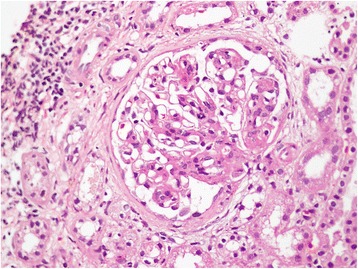

An ultrasound examination of our patient’s abdomen revealed normal-sized kidneys with increased echogenicity with mild splenomegaly.Blood film was reported as suggestive of anaemia of chronic disorder. In view of the bicytopenia and mild splenomegaly with significant hematuria, we performed a renal biopsy and a bone marrow biopsy. Results from the bone marrow biopsy showed no evidence of marrow infiltration by leukemia, lymphoma, myeloma or secondary deposits. The specimen from the renal biopsy (Figures 1 and 2) had 14 glomeruli, seen on the formalin-fixed paraffin sections. The glomeruli showed a mild diffuse increase in mesangial cells and matrix, and occasional tuft adhesions. Occasional foci of endocapillary proliferation were seen. The capillary basement membranes were normal. There were no crescents. We found focal infiltrates of lymphocytes in the interstitium. There were red cell and granular casts. We also noted occasional foci with tubular atrophy, interstitial fibrosis, and periglomerular sclerosis.

Figure 1.

Renal biopsy (×200 magnification). Diffuse increase in mesangial cells and matrix. Occasional neutrophils seen. Occasional foci of endocapillary proliferation seen. Focal parietal epithelial cell hyperplasia with occasional tuft adhesions. Capillaries are thickened but no double contouring or spikes were seen.